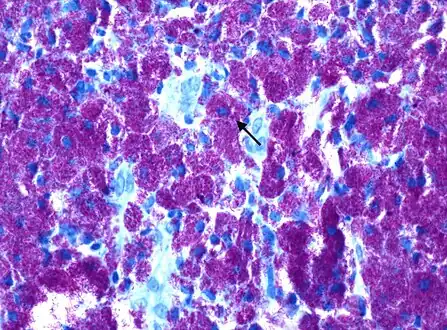

Mycobacterium avium-intracellulare infection, thin section from a lymph node [15] -

Rod-shaped bacilli with Kinyoun AFB stain shown densely packed within histiocytes, consistent with Mycobacterium avium complex